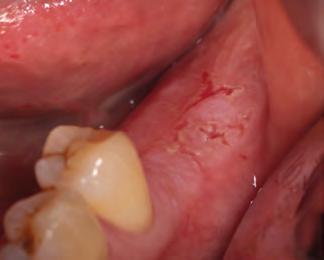

Surgical considerations

New parameters of restorative therapy require consideration of esthetic results that might require both periodontal and operative procedures to restore a harmonious integration and an esthetic balance of gingiva and tooth.34 Thus, periodontal plastic surgery procedures should be part of the clinician’s recipe for restoring the dentogingival complex. Traditionally, restorative therapy of teeth with gingival recession and carious or noncarious lesions has been achieved through operative procedures, with little attention given to the overall esthetic picture. In contrast, the perioesthetic approach considers the harmonious integration and interrelationship of the gingiva and tooth complex.35

In general, most clinical situations that present with gingival recession also involve a deficiency of keratinized attached gingiva, which requires mucogingival surgery.35 The periodontal plastic surgery procedures available for the treatment and correction of gingival recession include free gingival autografts, subepithelial connective tissue grafts, coronally positioned flaps, guided tissue regeneration, and acellular matrix grafts.36–41 These soft tissue grafts are indicated for the restoration of noncarious and carious cervical radicular lesions and for previously placed restorations associated with gingival recession. Recent advances in periodontal plastic surgery procedures have stimulated reassessment of the envelope technique and its modified version, the tunnel technique, for root coverage of single and multiple adjacent gingival recessions.36,42,43

The envelope technique originated in 1985 for single gingival recession defects.36,44 This procedure involved vertical incisions on either side of a tunnel preparation that

enabled placement of a subepithelial connective tissue graft within the tunnel to cover the gingival recession. The modified microsurgical technique eliminates the vertical incisions and allows the construction of a tunnel under the gingival tissue by means of a sulcular incision beyond the mucogingival line without raising a flap. This alteration of technique by using newly developed microsurgical instruments allows an undermining split-flap preparation of the facial tissues, ensuring improved blood supply, early wound healing, predictable root coverage, and esthetic postoperative results.45–53 This modified microsurgical approach simplifies the technique and allows for the treatment of multiple adjacent gingival recession defects in one surgical visit.

invasive preparationless procedure or with less conservative veneer preparations. The restorative materials discussed included injectable resin composites and ceramic (ie, feldspathic, pressable, machinable). For an optimal biologic framework and health, it was determined that connective tissue grafting would be necessary for treatment of the recessiontype defects on the maxillary left central and lateral incisors, canine, and premolars. The patient opted for the conservative preparationless composite veneers using the injectable resin technique followed by a connective tissue surgical procedure using the tunneling technique.